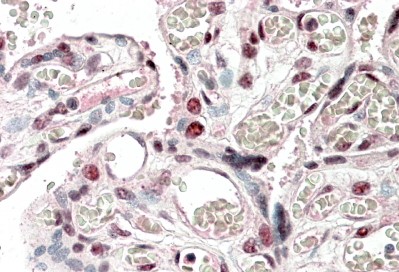

Product group Antibodies

ApplicationsWestern Blot, ELISA, ImmunoHistoChemistry

ReactivityHuman